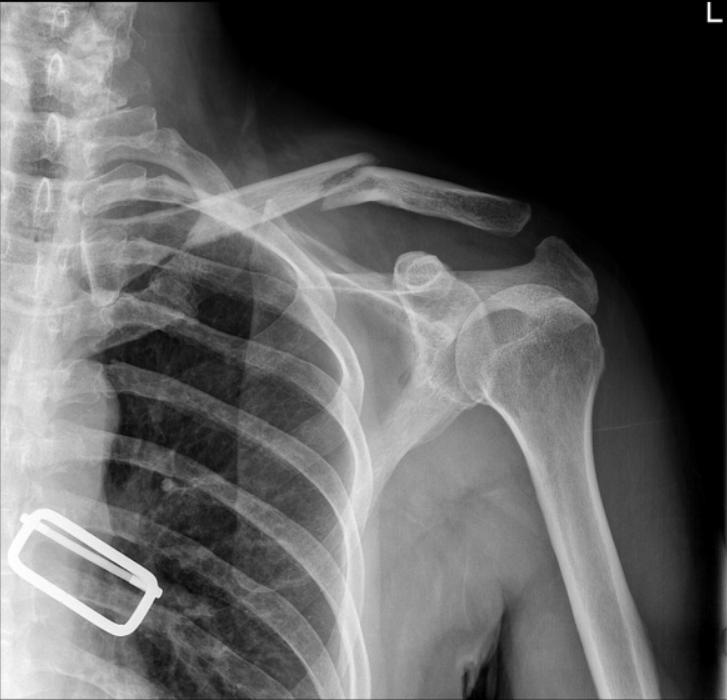

肩部正位平片显示锁骨中轴线状骨折,肩锁关节间隙无明显增宽,锁骨外侧端无明显增高